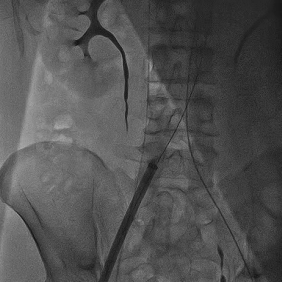

Step 1 冠状动脉造影及右窦中心造影

Step 2 瓣膜定位、释放

Step 3 瓣膜释放后造影